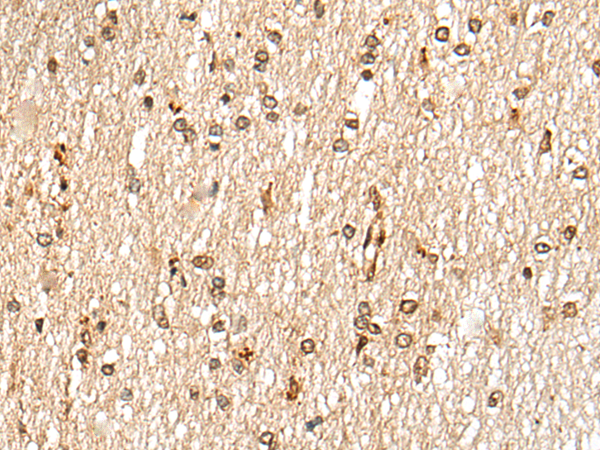

IHC positive control: |

Human thyroid cancer and human esophagus cancer |